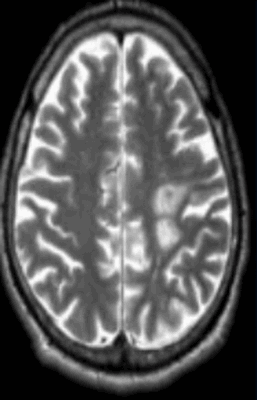

Очаги демиелинизации

Некоторые заболевания нервной системы сопровождаются повреждением глиальной оболочки длинных отростков нейронов. В результате патологических изменений нарушается проведение импульсов. Подобное состояние сопровождается неврологической симптоматикой различной степени интенсивности. Демиелинизация нервных волокон может быть вызвана:

- мультифокальной лейкоэнцефалопатией;

- рассеянным склерозом;

- диссимулирующим энцефаломиелитом;

- болезнью Марбурга, Девика и многими другими.

Обычно очаги демиелинизации выглядят как множественные мелкие участки гиперинтенсивного МР-сигнала, расположенные в одном или нескольких отделах головного мозга. По степени их распространенности, давности и одновременности возникновения врач судит о масштабах развития заболевания.